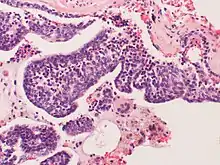

Pulmonary neuroendocrine cells (PNECs), are specialized airway epithelial cells that occur as solitary cells or as clusters called neuroepithelial bodies (NEBs) in the lung. Pulmonary neuroendocrine cells are also known as Kulchitsky cells or K cells.[2] They are located in the respiratory epithelium of the upper and lower respiratory tract. PNECs and NEBs exist from fetal and neonatal stages in the lung airways.

These cells are bottle- or flask-like in shape, and reach from the basement membrane to the lumen. They can be distinguished by their profile of bioactive amines and peptides, namely serotonin, calcitonin, calcitonin gene-related peptide (CGRP), chromogranin A, gastrin-releasing peptide (GRP), and cholecystokinin.

These cells can be the source of several types of lung cancer- most notably, small cell carcinoma of the lung, and bronchial carcinoid tumor.[3][4]